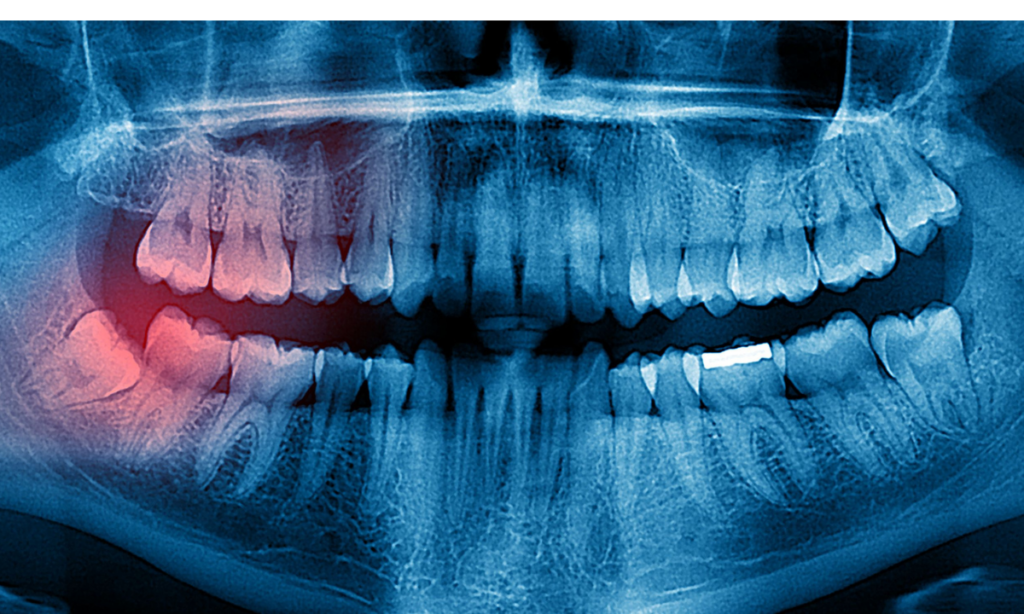

Wisdom Tooth Infection: 10 Warning Signs To Watch Out For

Wisdom tooth infection is one of the most common dental problems faced by young adults and adults alike. At our dental clinic in Whitefield, we often meet patients who confuse a simple wisdom tooth hurting with a more serious infection. The truth is, an untreated wisdom tooth impaction can silently lead to complications like swelling, […]